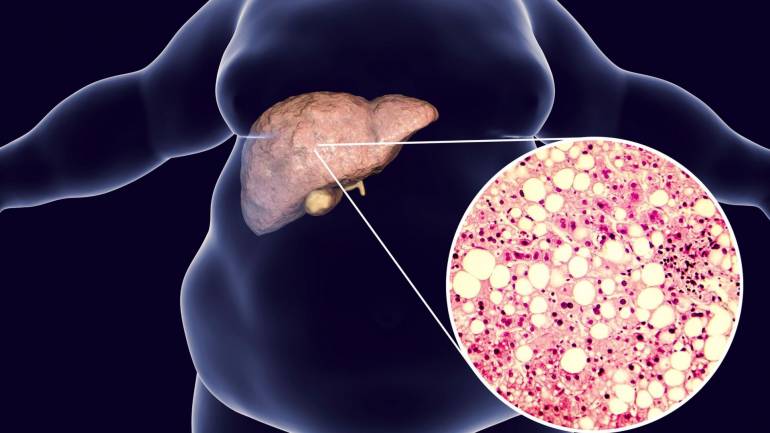

ไขมันพอกตับ คือ ภาวะที่มีไขมันสะสมในเซลล์ตับมากเกินไป โดยทั่วไปถ้าไขมันเกินร้อยละ 5-10 ของน้ำหนักตับ ถือว่าเข้าข่ายแล้ว ไขมันส่วนใหญ่เป็นไตรกลีเซอไรด์ (Triglycerides) ที่มาจากอาหารหรือการเผาผลาญผิดปกติ โรคนี้แบ่งเป็น 2 ประเภทหลัก ได้แก่

- NAFLD (Non-Alcoholic Fatty Liver Disease) ไขมันพอกตับที่ไม่เกี่ยวข้องกับแอลกอฮอล์ พบบ่อยในคนอ้วน ผู้ป่วยเบาหวาน หรือมีไขมันในเลือดสูง

น่าตกใจที่ 1 ใน 3 ของคนไทย มีภาวะนี้ และหลายคนไม่รู้ตัว เพราะไม่มีอาการในระยะแรก

ภาพประกอบข่าว

- อ้วนลงพุง ไขมันหน้าท้องสัมพันธ์กับการสะสมไขมันในตับ โดยเฉพาะคนที่มีดัชนีมวลกาย (BMI) เกิน 25 หรือรอบเอวเกิน 90 ซม. (ชาย) และ 80 ซม. (หญิง)

ระยะ 1 ไขมันสะสมแต่ยังไม่รุนแรง ไขมันเริ่มสะสมในเซลล์ตับเกินร้อยละ 5-10 โดยไม่มีอาการหรือการอักเสบ มักตรวจพบจากการตรวจสุขภาพ และสามารถย้อนกลับได้ด้วยการปรับอาหารและออกกำลังกาย